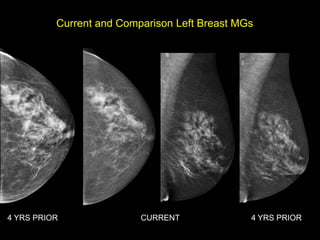

Current and Comparison Left Breast MGs

4 YRS PRIOR               CURRENT              4 YRS PRIOR